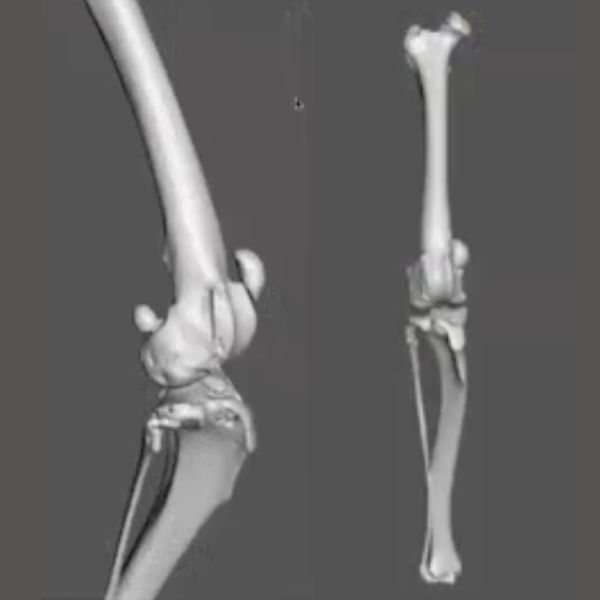

This is apparent in the CT renderings in Fig 7 (10:19) where a major translation of the tibial tuberosity has been simulated, resolving the frontal plane offset, but because of the unresolved significant femoral varus, the patella is tracking obliquely and quite abnormally through the trochlea. Even by forcing the patella to stay in place with a failed ridge replacement (Fig 8 10.54), you would still get abnormal tracking, erosion, and significant pain. An oblique trochlea creates abnormal patellar tracking and abnormal retropatellar pressures and is not a benign thing. So it is important to understand that managing more complex patella luxation cases is not just about keeping the patella from luxating.

With the tibia, it's less common to do a frontal plane corrective osteotomy than the femur, but again, it is all about measuring the angles, identifying the component deformities that are causing the luxation, and resolving the key deformities.

In the femur the frontal plane angles are referent to the anatomic axis of the femur. For the tibia, we use the mechanical axis, drawn from the center of the tibia proximally to the center of the tibia distally on a true craniocaudal radiograph or CT scan, and the proximal and distal joint reference lines. By convention the angulation of the frontal plane of the tibia is the mechanical Medial Proximal Tibial Angle (mMPTA), and the mechanical Medial Distal Tibial Angle (mMDTA), which are approximately 93° and 96° respectively. Most commonly MPL is associated with tibial valgus deformities with increased mMPTA.